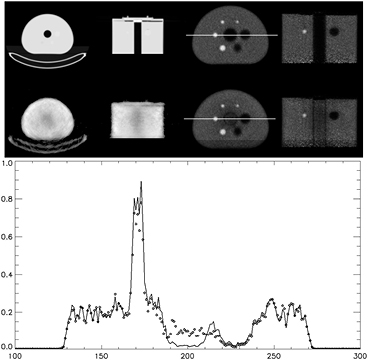

An image quality phantom was scanned to extend the study to a torso sized object. The phantom was filled with Ge-68 in an epoxy matrix and had an activity approximately 2 mCi at the time of the measurement. The phantom has 6 spheres with 4 hot (4x activity concentration from background) and 2 cold spheres with a cold Styrofoam filled cylinder in the center of the phantom. The phantom was placed in the centered to the bore and set on top of the bed in a foam holder for this particular phantom. A CT was performed before the phantom was moved into the PET field of view. The listmode acquisition was performed for 30 min. The emission data was rebinned for 10 min acquisition time and all 30 min of transmission data for the 307 keV photons were rebinned for transmission data. The longer transmission scan was performed to account for the exclusion of 202 keV transmission data due to observed contamination of the 202 keV transmission data from the emission data.

Figure 10 shows the derived attenuation maps from the CT scan and from 30 min of transmission data from Lu-176. From the attenuation maps, it is observed that the cold cylinder in the Lu-176 transmission image is not well resolved. The corresponding PET emission images show some artifacts that come from having residual values in the cylinder that should be empty. This problem is not seen in the cold spheres because the spheres are filled with epoxy. The cross talk between the emission data and the attenuation map puts activity in the region where there should be air and no activity.

Figure 10. Attenuation maps derived from CT (top left) and from Lu-176 (bottom left). Images on the right are PET emission data reconstructed with 10 min of emission data from ~2 mCi of Ge-68. Lower plot is of the profile across the images shown by the white line in the above images using attenuation maps from CT (-) and Lu-176 (◊).

Download figure:

Standard image High-resolution image3.5. Reconstruction of emission data with Lu-176 transmission data and MLACF